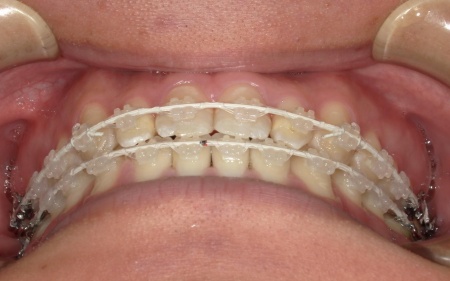

20代男性 受け口のように見える切端咬合をセラミックブラケットによる矯正治療で改善した症例

拝見したところ、上下前歯の先端同士が触れ合う「切端咬合(せったんこうごう)」の状態でした。

通常は上前歯が下前歯をわずかに覆うように重なりますが、患者様の場合は上下前歯の先端がほぼ同じ高さで噛み合っているため、受け口のような印象がみられました。

患者様は「できるだけ目立ちにくい装置を使用したい」とのことから、②のセラミックブラケット矯正を選択されました。

まず、下奥歯(臼歯)を歯茎の外側に持ち上げる「挺出(ていしゅつ)」という処置を行いました。

奥歯が少し高くなることで、下顎全体がわずかに後ろへ動くため、前歯の噛み合わせが整いやすくなります。